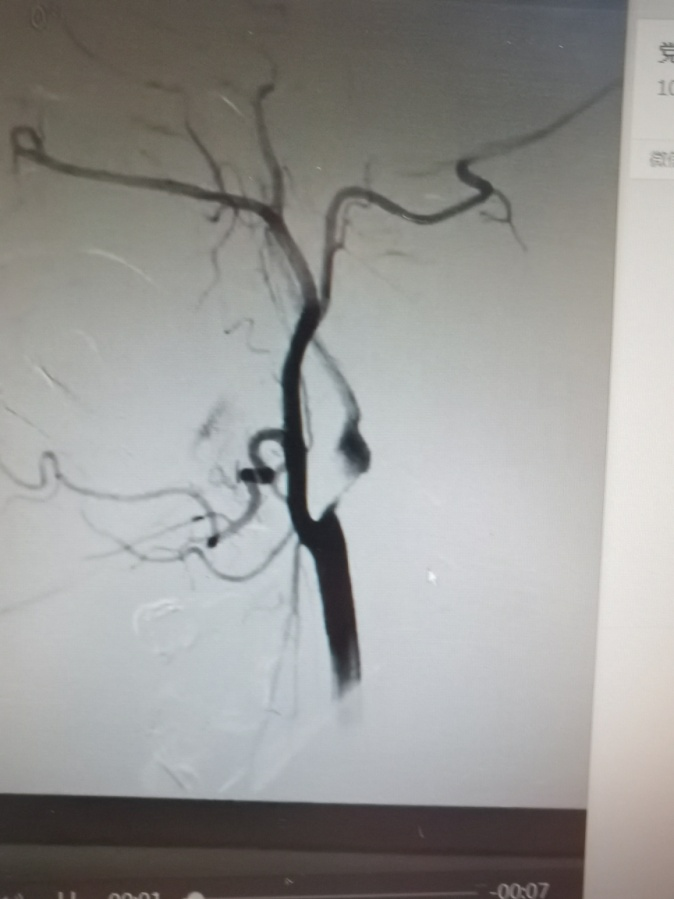

圖1.患者左側(cè)頸內(nèi)動脈起始段重度狹窄。

圖3.患者術(shù)后復(fù)查頭頸部CTA顯示左側(cè)頸內(nèi)動脈管腔無狹窄,血流通暢。